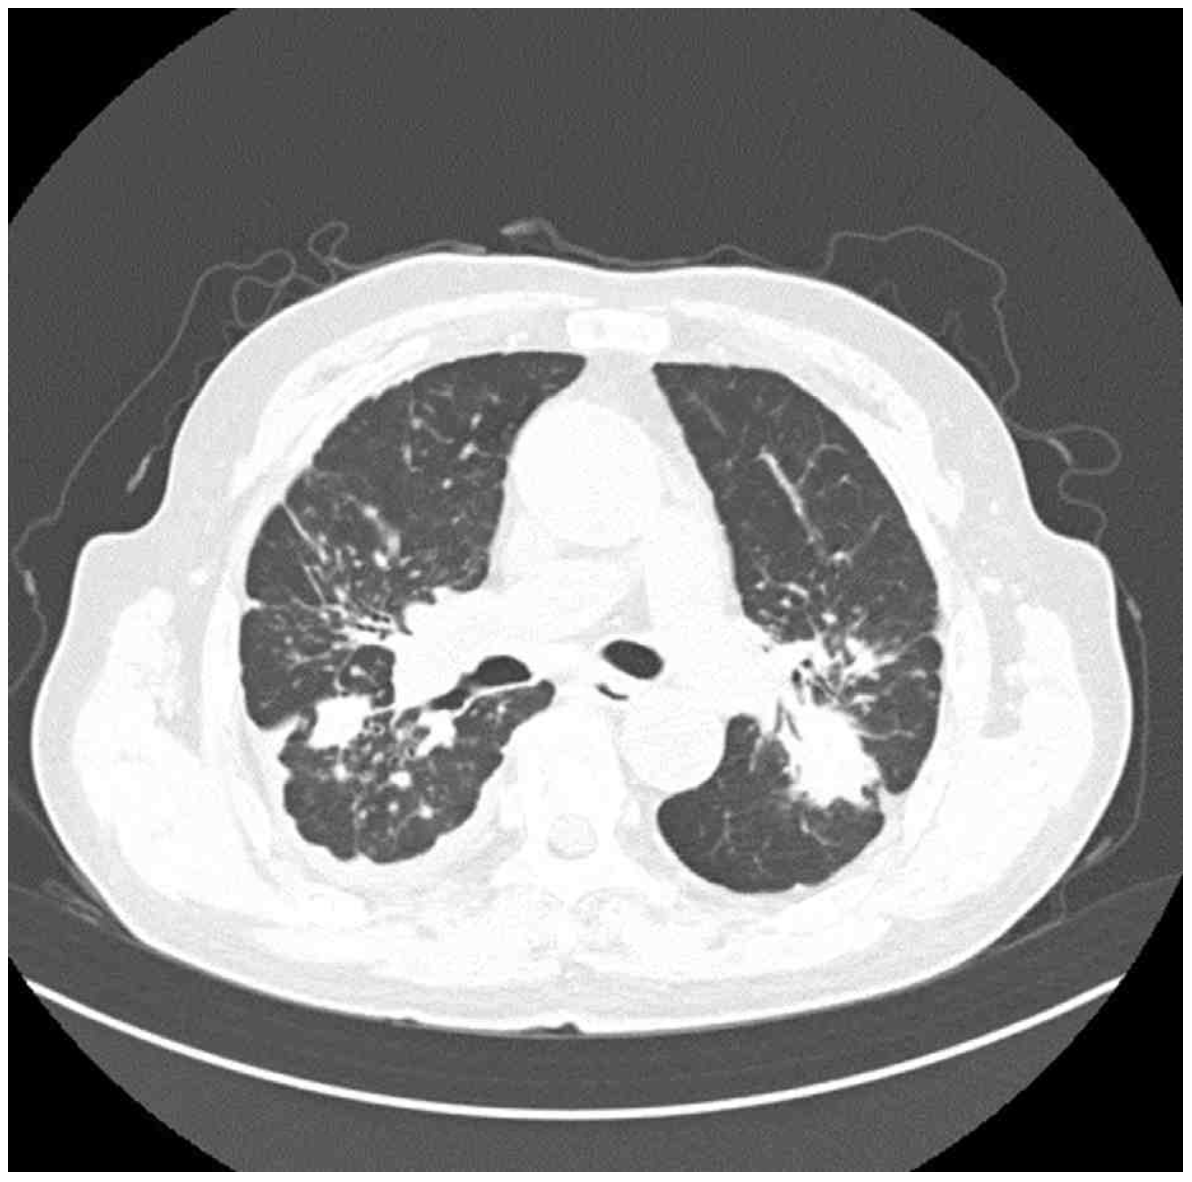

CXR: Bilateral patchy consolidation

CT: Multiple nodules, masses, GGO

• 흉부 X선 검사에서 양측 폐야에 patchy consolidation이 관찰되었으며, 흉부 컴퓨터단층촬영에서 다수의 결절, 종괴 및 간유리 음영이 확인되었다. 특히, 상엽 부위에서 대칭적으로 위치한 종괴가 관찰되는 점을 고려할 때 규폐증으로 인한 진행성 거대 섬유화 가능성이 높다고 판단된다.

• 규폐증을 진단하기 위해서는 silica에 대한 노출력, 특징적인 영상 소견, 그리고 유사한 증상을 유발할 수 있는 다른 폐질환이 배제되어야 한다. 해당 환자의 경우, 22년간의 직업력과 진행성 거대 섬유화를 시사하는 영상 소견이 확인되고 있으며, 타 질환을 의심할만한 소견이 제시되지 않았으므로 만성 규폐증으로 진단할 수 있다.